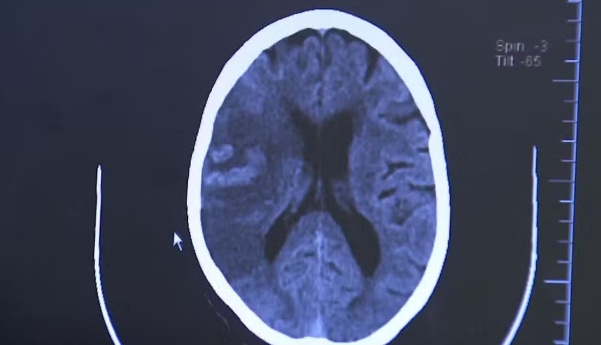

O diagnóstico é feito por tomografia computadorizada ou ressonância magnética do crânio. “Esses exames permitem detectar a área afetada e definir se é um AVC isquêmico ou hemorrágico”, diz Chaddad.